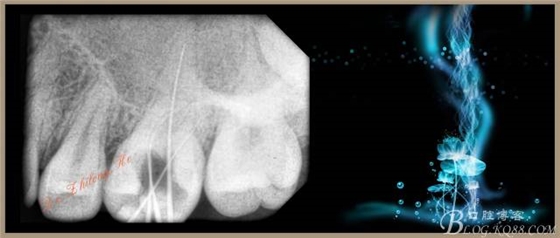

4、試主尖,側(cè)壓充填法根充,拍根充片,聚羧酸鋅暫封。

1、上頜磨牙近中頰根常有兩個(gè)根管,即MB、MB2,近年來(lái)研究表明上頜磨牙MB2的發(fā)現(xiàn)率大于60%,MB2的遺漏是上頜磨牙根管治療失敗的重要原因之一。熟悉、掌握MB2根管口的定位,有助于臨床醫(yī)師發(fā)現(xiàn)MB2,提高上頜磨牙根管治療的成功率。下面是MB2根管口的定位方法(僅供參考):

①M(fèi)B-MB2距離為(1.47±0.54)mm;

②MB-P的距離為(5.77±0.66)mm;

③MB2根管口與MB-P連線的垂直距離為(0.53±0.28)mm;

④MB-P連線與MB-MB2連線的夾角為23.07°±13.08°;

⑤MB2位于MB舌側(cè)2mm以內(nèi)及MB-P連線近中1mm以內(nèi)。